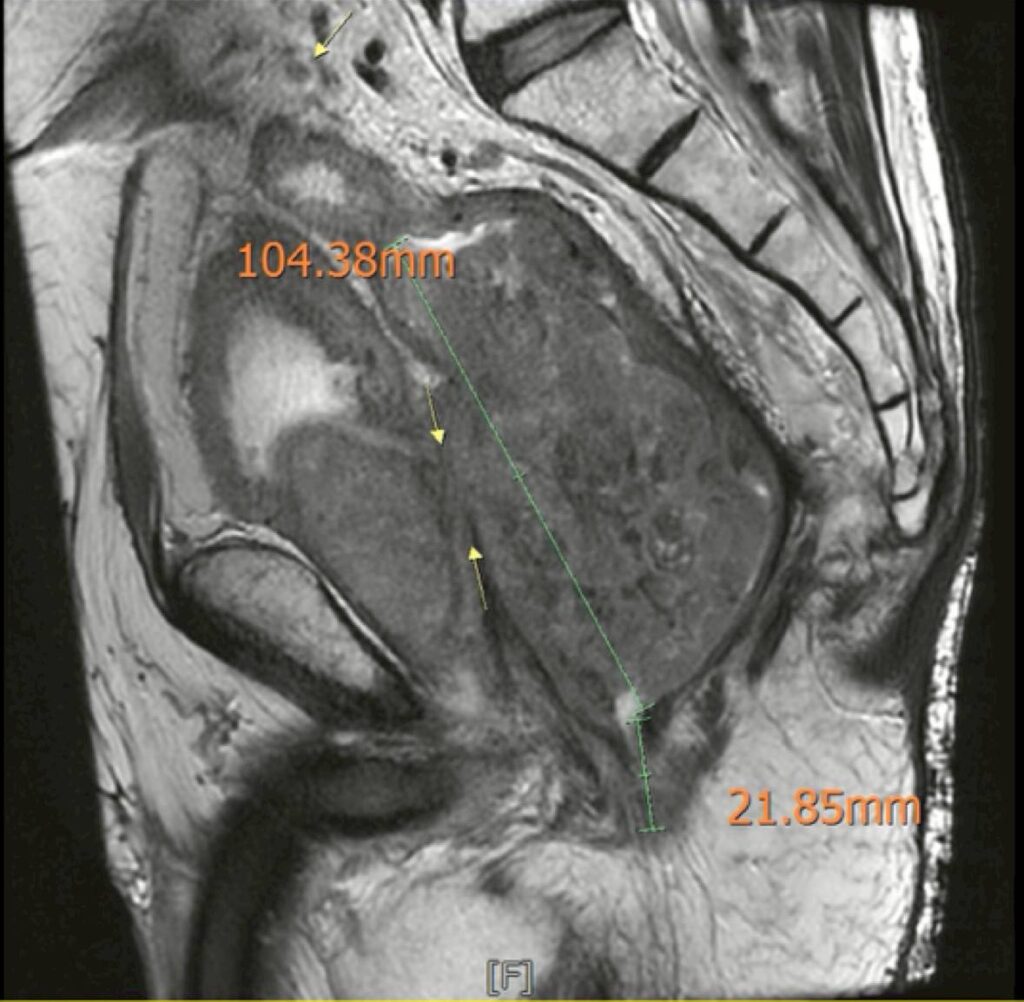

在感染穩定之後,黃晟瑋醫師重新安排影像檢查,結果顯示:腫瘤處於穩定狀態,沒有遠端轉移,也沒有明顯惡化。這代表一件很重要的事情─腫瘤仍然有機會透過手術完整切除。

手術當天,手術團隊進行了骨盆複雜腫瘤清除手術(Pelvic Exenteration),手術內容包括:全直腸與肛門切除、膀胱與攝腺切除、骨盆腔淋巴結清除、部分薦骨神經切除、會陰部受侵犯軟組織廣泛切除、建立永久人工肛門與泌尿造口、整形外科皮瓣重建會陰部傷口、這是一場非常大型且複雜的手術,但手術順利完成。